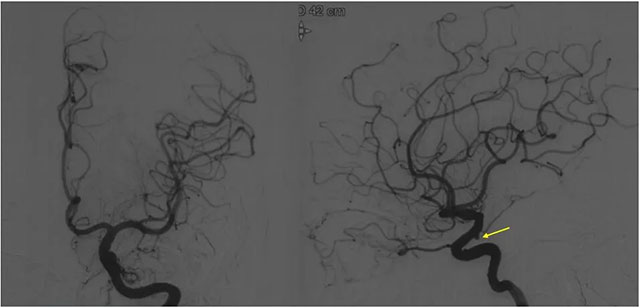

▲ 微导管造影确认后,注入 Onyx 18胶 5ml

经左侧股动脉以单弯造影管超选至左侧颈总动脉造影明确静脉穿刺点入路,予以穿刺针穿刺成功后造影明确在位,随后 Echelon 10微导管到位横窦,填入一枚弹簧圈做塞子,造影明确位置后,缓慢注入 Onxy18胶 5毫升,铸胶弥散良好,通过静脉逆向弥散至部分供血动脉内。复查造影,见瘘口完全被栓塞,引流静脉消失,手术成功。